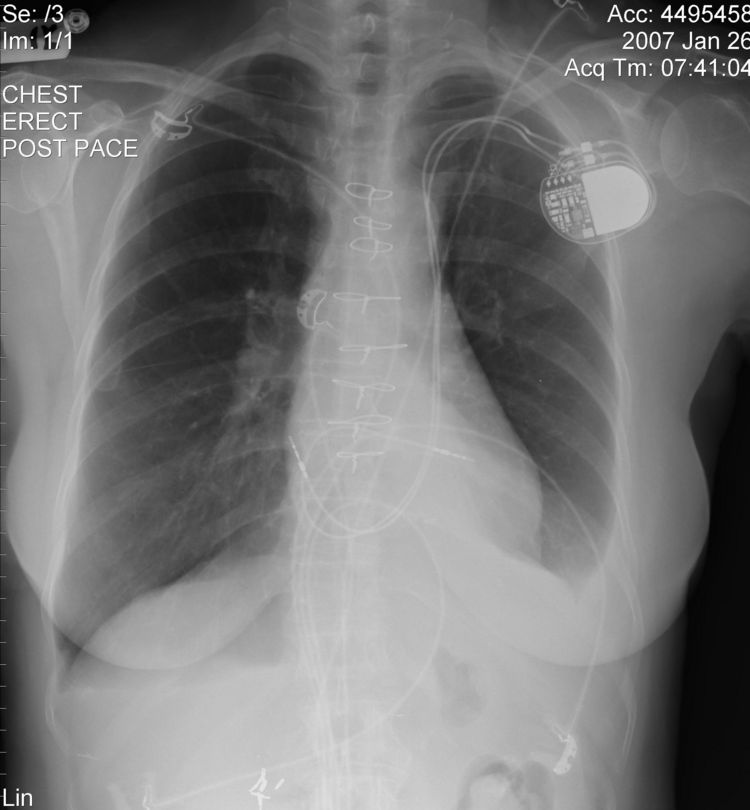

The above CXR show the atrial and ventricular pacemaker lead passing through a persistent left sided SVC.